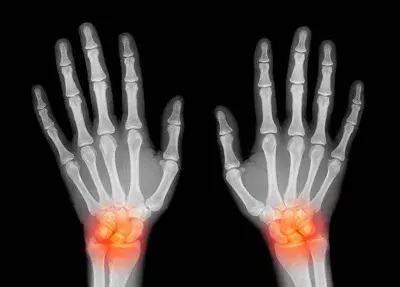

神经损伤更多见的是慢性神经劳损,而且往往不容易发现。和手部相关的慢性神经损伤多见于肘部和腕部。慢性劳损后局部增生、骨折后畸形愈合、先天性结构异常或局部长肿物均可能导致神经通路变窄,在关节活动的时候,受压的神经与周围的结构不断摩擦,比较容易发生局部水肿、增粗,又进一步加重了神经卡压。

临床表现

运动功能障碍:表现为肌张力低下,肌肉迟缓性瘫痪,肌肉萎缩,肢体姿势异常。

感觉功能障碍:主观感觉障碍,如在没有外界刺激的情况下出现感觉异常、自发疼痛、幻痛等;客观感觉障碍:如感觉丧失、感觉减退、感觉过敏等。

反射异常:如深、浅反射均减弱或消失。

自主神经功能障碍:可表现为刺激性损伤和破坏性损伤,刺激性损伤如皮肤发红、潮湿、角化过度等,破坏性损伤如皮肤发绀、冰凉、干燥等。